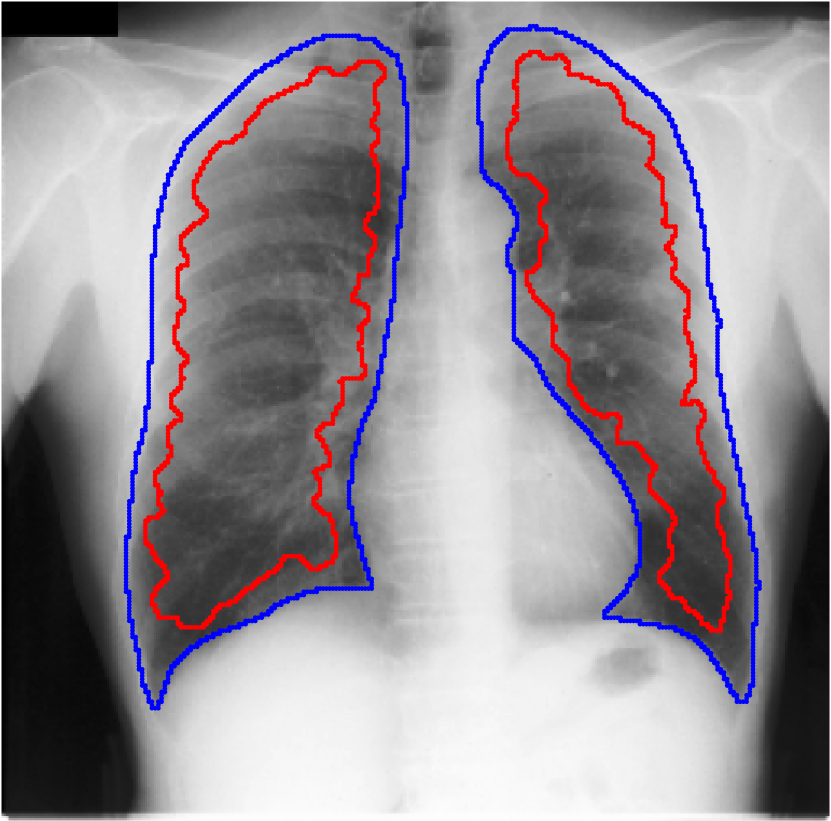

Table 1 shows the segmentation results of different methods with synthetic noisy label settings on JSRT , ISIC 2017 and Brats 2020 dataset. Note that QAM cannot be applied to Brats 2020 dataset because their network is designed for 2D only. We compare DICE score (DSC) on testing sets (against the clean labels). For each setting, we train 5 different models, and report the mean DSC and standard deviation. In and , where biases show up in noisy labels, the proposed method outperforms the baselines by a big leap in total case. The compared methods, however, only work when little bias is included, like . is equivalent to setting in our Markov model, resulting in . We also test the proposed method on real-world label noise, results shows in Table 2. Figure 5 shows examples of label correction results. We provide more qualitative results in the Appendix A.4.

A.4 Qualitative Results